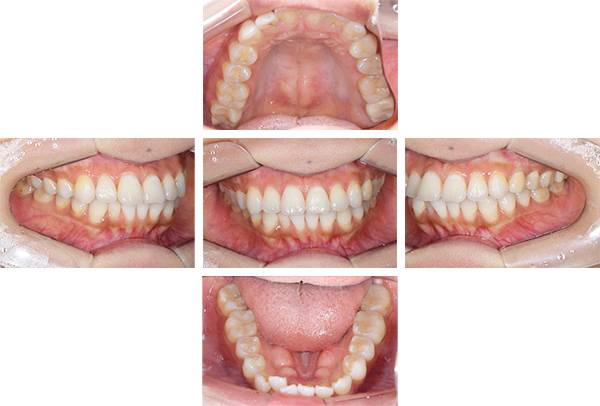

インレー症例

治療前

治療後

治療期間 8回(2ヶ月)

費用 ・セラミックインレー9本

合計:495,000円

治療リスク・副作用 ・詰め物、被せ物をする時は自分の歯を削ることになります

・歯ぎしり・食いしばりが強い方は、セラミックが割れてしまうことがあります。